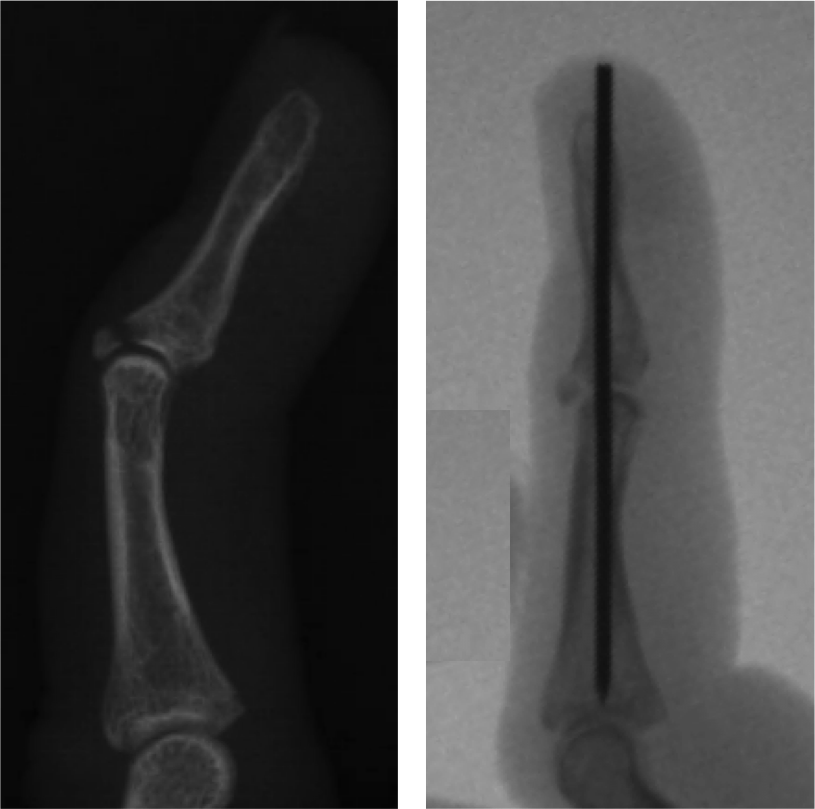

From radiopaedia.org

Mallet finger Image Mallet Finger Not Healing mallet finger is a deformity of the finger caused by injury to the extensor tendon or the bone. mallet finger is a common sports injury that makes the tip of the finger bend and cannot be straightened. mallet finger is a condition where the tip of the finger cannot straighten due to a tendon injury. mallet. Mallet Finger Not Healing.